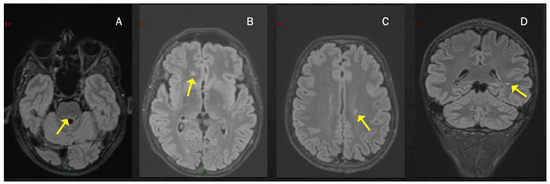

2. MS Onset after SARS-CoV-2 Exposure